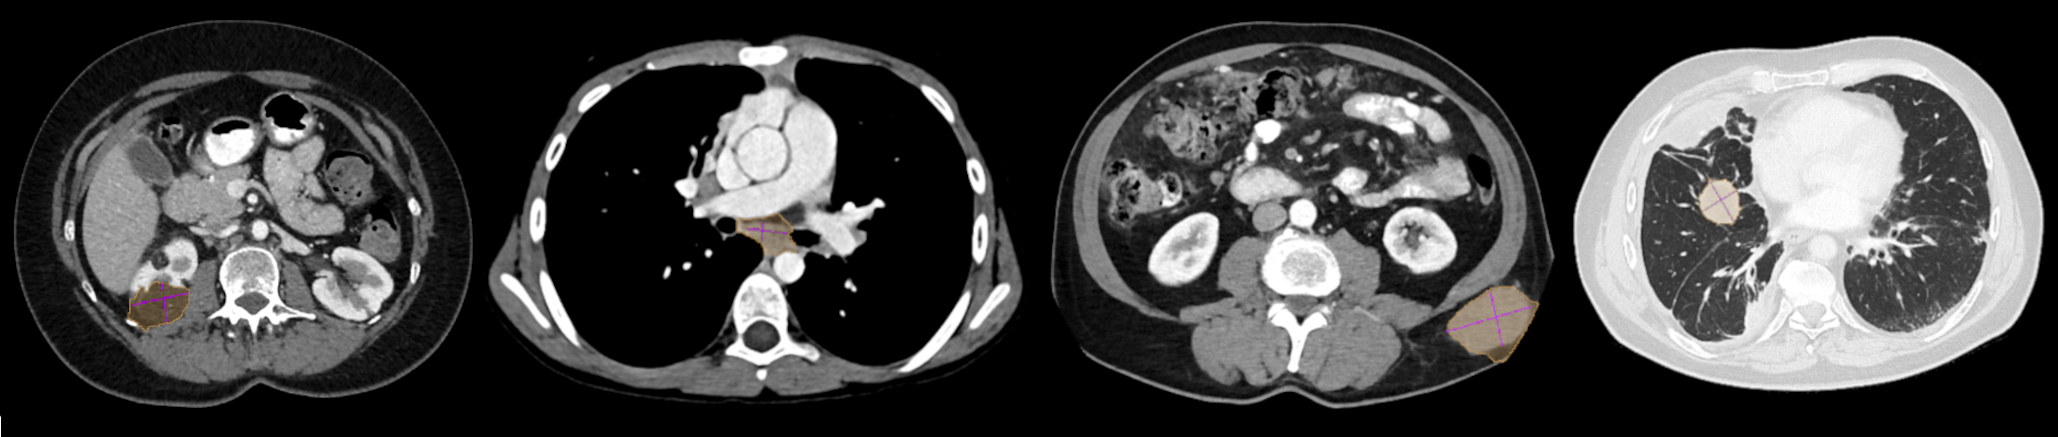

Pseudo-masks were generated using the Grabcut algortihm [Rother et al., 2004], expanding on the approach of Cai et al. [2018]. GrabCut requires declaring four different image seeds: probable foreground (PFG), probable background (PBG), foreground (FG) and background (BG) regions. We used a dilation of the bounding box fitted to the RECIST measurements as PB. The area outside of this bounding box was set as BG. For the foreground definition we fit an ellipse to the lesion measurements. A dilation of this ellipse is used as PFG, whereas an erosion is set as FG. For each lesion we apply GrabCut multiple times. Initially, with the image normalized to the window level provided in the metadata. Subsequently, normalized to the average of the fitted elipse ±plus-or-minus\pm 50 and 100 Hounsfield units. We then chose from the GrabCut masks or directly utilized the ellipse fitted to the measurements, based on the calculation of the measurement error of each mask in comparison to the original measurement. Figure 2 shows examples of pseudo-masks extracted using GrabCut. As can be seen in these examples, using GrabCut frequently leads to over- and under-segmentation on challenging lesions.

Refer to caption

Figure 2: Examples of GrabCut pseudo-masks. From left to right, a kidney lesion, mediastinal lymph node, subcutaneous mass, and lung lesion. Note how GrabCut tends to oversegment (orange mask \blacksquare) into healthy tissues compared to the reference measurements (purple lines \blacksquare). Lung lesions are visualized using Window Level: -500 HU, Window Width: 1400 HU. Lesions outside the lungs with WL: 350 WW: 40.